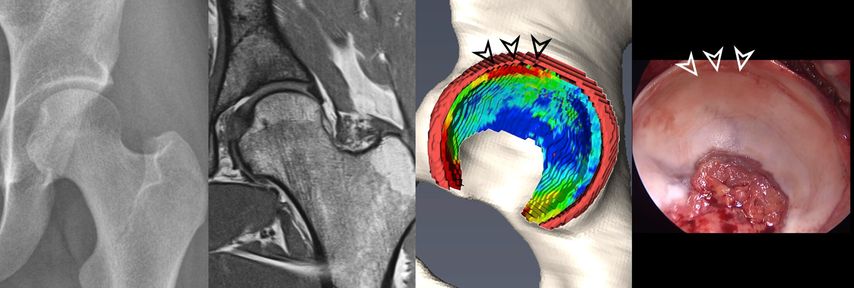

Fig. 3: Two patients with cam deformity of the proximal femur. Pelvic X-ray shows in both cases only mild arthritic changes. The morphologic MRI only allows 2D morphologic assessment of damage. The 3D cartilage models allow for a quantitative and 3D assessment of cartilage degeneration. Compared to the patient with good cartilage quality (blue color coding) who underwent impingement surgery the patient below showed too advanced signs of cartilage damage (red color coding) and thus underwent total hip replacement.

More recently, we introduced a deep-learning-based approach for automatic segmentation of hip cartilage and labrum using a 3D dGEMRIC sequence (MP2RAGE). The approach allows for automatic and reliable generation of 3D models of hip cartilage and labrum within seconds, and providing both 3D morphologic information of the hip joint as well as color-coded dGEMRIC indices for quantitative analysis of cartilage damage (Fig. 2 & 3).19

As mentioned above, hip MRI assessments are based on selected 2D images. Creating 3D models requires manual segmentation, which involves dividing an image into multiple regions of interest based on pixel properties. This process is done slice by slice, making it very time-consuming and impractical for routine clinical use and is affected by inter-observer variability even when performed by an expert. Deep learning, a branch of machine learning, has shown great promise in automating image segmentation. Convolutional neural networks, particularly those with U-net architecture, are commonly used for this purpose. More recently, the nnU-net, an extension of the U-net, was introduced. It automatically configures itself for biomedical image segmentation and has produced excellent results across various medical imaging tasks.15 Compared to other joints such as the knee automatic segmentation of hip cartilage is more challenging due to its naturally thinner structure and oblique orientation. Previous attempts to automate hip cartilage segmentation were based on small sample sizes and did not include the labrum.16–18 Ideally, combining a 3D analysis of chondro-labral morphology with cartilage composition would enable an improved analysis of chondro-labral dimensions and of the severity of joint damage (Fig. 2 & 3).